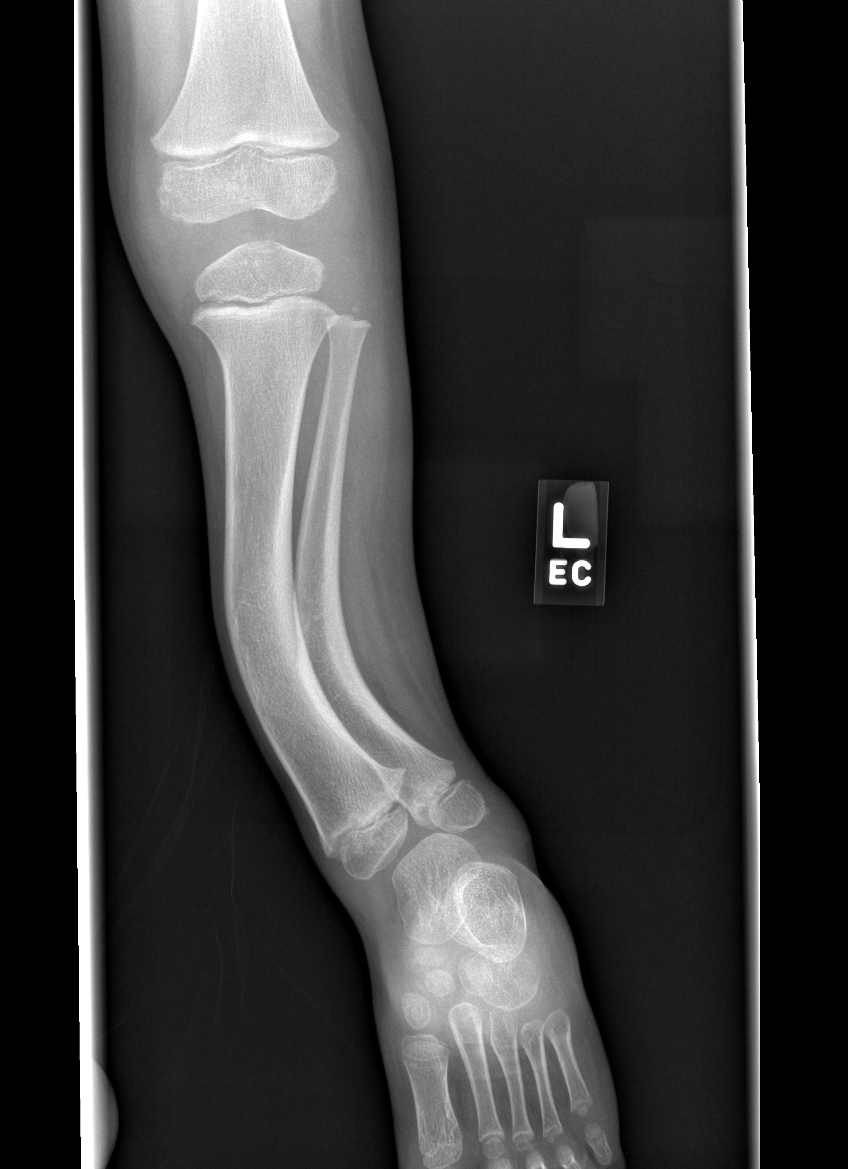

Section 1 Submit Findings CB1550 Findings Skeletal Survey - Technique Check Skull AP/Lat Yes No Cervical and Thoracolumbar spine Yes No Chest X-Ray Yes No Ribs – Left/Right Oblique Yes No Abdominal X-Ray Yes No Pelvis with both hips Yes No Bilateral Humerus, Forearm, Hand Yes No Bilateral Femur, Tibia/fibula, feet Yes No Any additional lateral views of the extremities Yes No The exam is over or under penetrated. Yes No The exam may or may not be limited by overlying structures or soft tissues, body habitus, patient positioning, support devices, or motion. Yes No The area of concern is indicated by the patient, technologist, or care provider. Yes No The area of concern is included on the exam. Yes No Soft Tissues There is soft tissue swelling, indistinctness of fat/muscle planes, gas, or laceration in the area of clinical concern. Yes No There is an effusion, fat pad displacement, or fat fluid level. Yes No There is a radiodense or lucent foreign body. Yes No There are other densities, calcifications, post-surgical changes, or support devices in the soft tissues. Yes No Any support lines/tubes. Yes No Bone There is a break or interruption of the continuity of the cortical or cancellous bone. Yes No There is overriding of the trabeculae with apparent sclerosis. Yes No There is displacement of a fracture fragment. Yes No There is bowing of the bone in addition to the fracture at the apex of the bowed bone concerning for the greenstick. Yes No There is a spiral fracture of the leg concerning for toddler’s fracture. Yes No There is abnormal angulation or bulging of the cortical surface relative to the normal cortex which could be from a buckle or torus fracture. Yes No There is a displaced fragment which may be from avulsion by a tendon, ligament, or joint capsule or from a comminuted or other fracture. Yes No The stress trabeculae or other trabeculae of the cancellous bone are interrupted or otherwise abnormal. Yes No There is subperiosteal or endosteal reaction which could indicate a healing or subacute fracture or other abnormality. Yes No There is hard/soft callus formation. Yes No There is remodeling of the bone. Yes No There is a corner fracture or metaphyseal lesion that could be from nonaccidental trauma. Yes No There are multiple fractures of different ages. Yes No There are vertebral body/spinous process fractures. Yes No There are rib fractures. Location - posterior or lateral. Yes No There is scapular/sternal fracture. Yes No There are fractures of the digits. Yes No There are wormian bones. Yes No There are intrasutural bones. Yes No There is metaphyseal abnormality (lucencies, increased density, erosion) which may be from something other than injury such as stress, metabolic disease (e.g. rickets with loss or distortion of the zone of the provisional calcification), neoplasm (e.g. leukemia), heavy metals, inflammation, or infection. Yes No There are metaphyseal spurs. Yes No There are bony deformities involving multiple bones. Yes No The bones are gracile. Yes No There are non-healing fractures. Yes No There is/are focal or multifocal lytic/lucent, blastic/sclerotic or mixed density lesion(s) or other abnormality. Yes No Overall bone density is increased or decreased with or without thinning or thickening of the cortical or cancellous bone. Yes No Growth plates, ossification centers, apophyses The growth plate(s) is/are abnormal. Yes No There is widening of the physis from a fracture with or without displacement of the epiphysis (Salter-Harris I). Yes No There is a fracture through the physis which then extends into the metaphysis with or without angulation or displacement (S-H II). Yes No There is a fracture through the physis which then extends into the epiphysis and is intra-articular, with or without angulation or displacement (S-H III). Yes No There is a fracture through the metaphysis, physis, and epiphysis which extends into the joint space with or without angulation or displacement (S-H IV). Yes No There is narrowing of the physis from a compression fracture (S-H V). Yes No The apophysis, epicondyle, secondary ossification center, or accessory ossicle is displaced or otherwise abnormal. Yes No The ossification centers are underdeveloped. Yes No Joints and alignment There is an effusion, fat pad displacement, or fat fluid level. Yes No The epiphysis or subchondral bone is fractured, interrupted, flattened, compressed, impacted, displaced, or otherwise abnormal. Yes No There is an intra-articular loose body or chondrocalcinosis. Yes No The joint is widened, narrowed, dislocated, malaligned, or incongruent. Yes No There is pseudoarthrosis. Yes No Other findings There are developmental changes or other anatomic variants or other existing conditions that may or may not be contributing to symptoms which can or should be further evaluated non-emergently or are otherwise incidental. Yes No The remainder of the exam is abnormal for age. Yes No The lungs show focal airspace opacity. Yes No There is pneumothorax. Yes No There is organomegaly. Yes No There is intra-abdominal calcification. Yes No There is displacement of the bowel loops. Yes No There is free intraperitoneal air. Yes No The bowel loops are dilated/obstructed. Yes No There is paraspinal soft tissue abnormality. Yes No